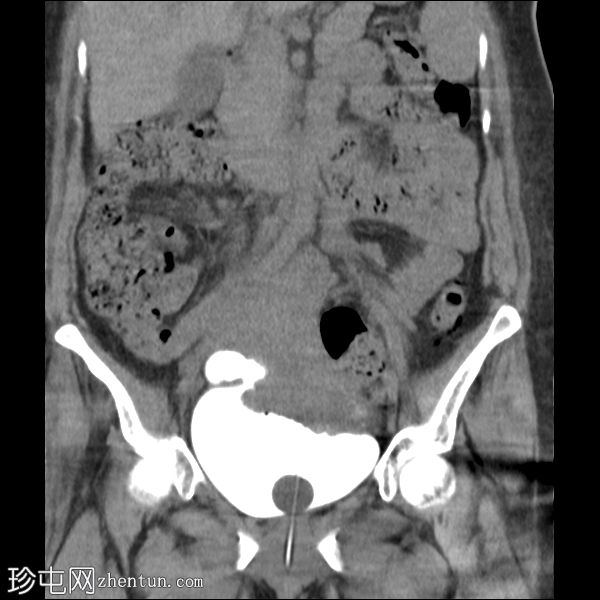

冠状位

CT膀胱造影显示右骨盆内局部膀胱外造影剂积聚,源自膀胱。

膀胱扩张,Foley球囊置入。

子宫体积大,前倾,内可见气室,似为产后变化。

检查结果符合医源性膀胱破裂,经手术证实。

膀胱外造影剂积聚与膀胱相连,提示膀胱破裂。

医源性膀胱破裂通常是腹膜内损伤,需要手术修复。